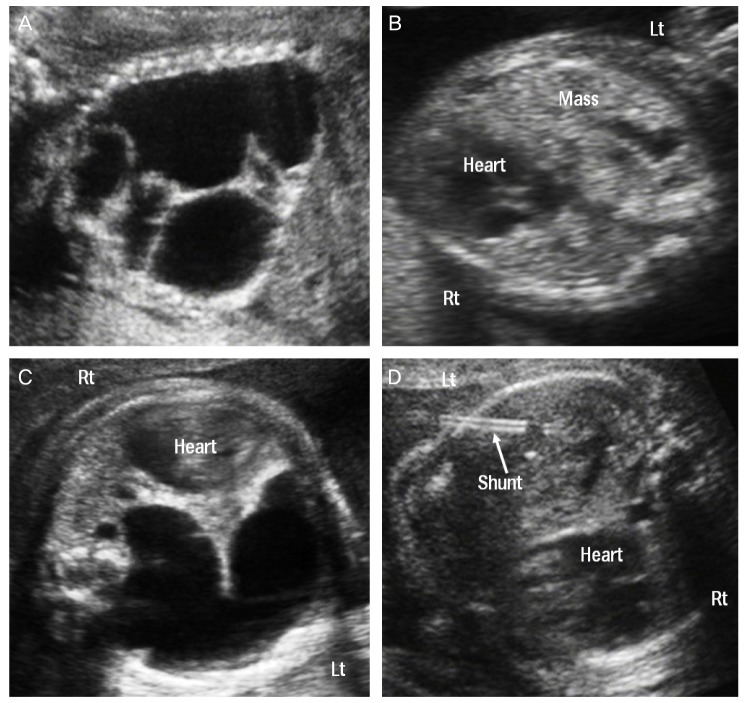

One of our six cases was treated with OK-432 (case 5) (Fig. 2). An aspiration of 45 mL of cystic fluid followed by injection of 0.07 KE (0.7 mL) was performed at 23.2 weeks of gestation. This procedure was repeated twice with increased does of OK-432 (0.12 and 0.2 KE, respectively). Although there was a subsequent marked reduction in the size of the cyst after each injection of OK-432, the fluid was found to have reaccumulated at the 1 week follow-up. Therefore shunting was performed at 26.4 weeks of gestation. Thereafter the mean size of the largest cyst within the CCAM was decreased.

Fig. 2.

Case 5 fetus with macrocytic CCAM who were treated with injection of OK-432 and thoracoamniotic shunting. (A) Before the procedures. (B) After injection of OK-432. (C) The cystic mass was redeveloped at the 1 week follow-up. (D) After shunting, the cystic mass was almost disappeared. Lt, left; Rt, right.